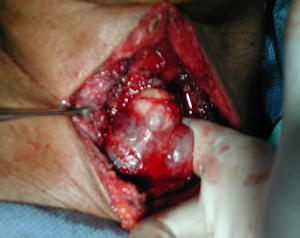

Figura 3 -

• Observe el tumor del mediastino ahora que esta en el cuello, de tamaño y características como las descritas por los estudios.

•     El tumor del mediastino una vez que está en el cuello, se comprobó que (a diferencia del caso anterior ) , forma cuerpo con la porcion izquierda residual de la glándula tiroides, se libera y se reseca en bloque y se envió completo para anatomía patológica. Se conservó una pequeña porción de tiroides residual del lado derecho.